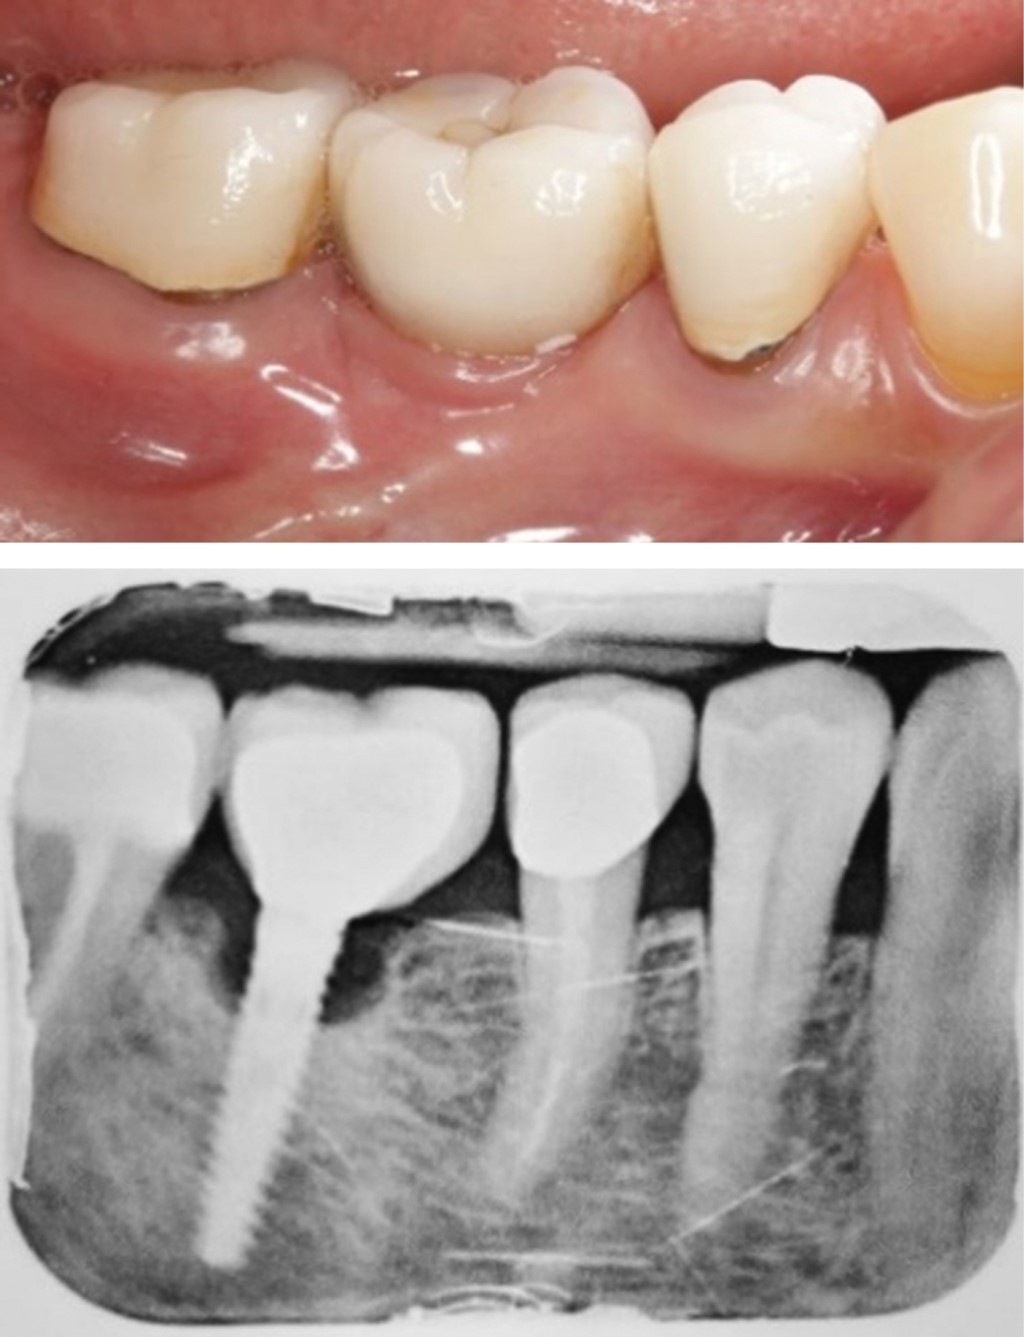

A la exploración clínica se observó la presencia de implantes dentales en los sitios de los dientes 16, 15, 37, 36 y 46; dichos implantes mostraron al sondeo profundidades mayores de 6 mm en todos los sitios, lo mismo que presencia de sangrado al sondeo y dolor. Las restauraciones de los implantes se observaron en buen estado y la posición de los implantes parecía correcta. A la exploración radiográfica, se detectaron pérdidas óseas mayores a 3 mm en todos los implantes. Con lo anterior se emitió el diagnóstico de periimplantitis para los cinco implantes que tenía la paciente.

Manejo del caso. Después de haber referido a la paciente a su médico tratante para su correcto control glucémico, se inició la terapia no quirúrgica para la periimplantitis, la cual consistió en el correcto control personal de placa, eliminación del biofilm microbiano supragingival y subgingival con ayuda de copas de hule y curetas de titanio e irrigación subgingival con peróxido de hidrógeno al 3%. Tres semanas después se realiza una revaloración de los defectos y se decide tratar el implante del diente 46 mediante un abordaje reconstructivo, puesto que presentaba un defecto de tipo intraóseo (Figura 1). Los otros implantes se abordaron mediante una terapia reparativa, dada la configuración de tipo horizontal de los defectos óseos.